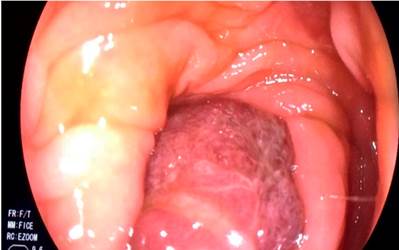

Durante la hospitalización, el paciente presentó una agudización de los síntomas, que se agravó por una rectorragia. Por este motivo, se solicitó realizar una colonoscopia total, en la cual se observó un gran pólipo pediculado de 40 mm, con un pedículo largo de aproximadamente 30 mm en el colon sigmoide, que mostró un prolapso causado por peristaltismo, lo que generó una obstrucción de la luz colónica (Figuras 1,2,3 y4). La cabeza del pólipo estaba erosionada como una probable causa de rectorragia.

Figura 2 Pólipo del colon que ocluye en su totalidad la luz colónica.